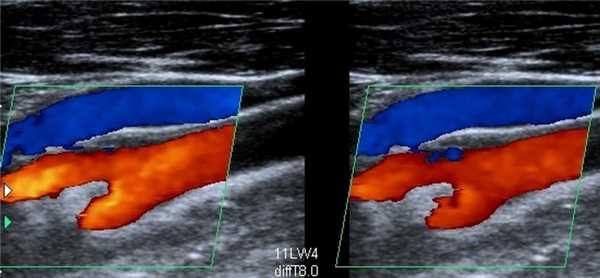

Непосредственно перед процедурой ЭВЛК проводится УЗИ варикозно расширенных сосудов — определяется диаметр, протяженность и расположение пораженных участков. После этого под непрерывным УЗИ-наблюдением хирург размечает на коже расположение варикозных расширений вен, которые необходимо обработать лазером, и выполняет местную анестезию кожи в той области (чаще всего около лодыжки или в верхней трети голени), где будет сделана пункция большой подкожной вены [4], [5].

Наиболее информативный метод диагностики — дуплексное УЗИ. Исследование проводится при наличии симптомов для установления диагноза и для регулярного контроля за состоянием вен. Специалисты рекомендуют проводить его 1-2 раза в год. Безопасная информативная процедура показана в любом возрасте, она безболезненна и может проводиться неограниченное число раз. Ультразвуковое исследование занимает примерно 20-30 минут. На дисплее врач видит изображение, полученное с помощью перемещаемого по коже датчика, и определяет состояние вен и клапанов, наличие или отсутствие тромбов.

Выбирая методику, больные часто интересуются, как происходит удаление вен лазером. Этот современный способ лечения измененных варикозом сосудов заключается в термическом воздействии. Лазерный световод вводится во внутрисосудистый просвет и продвигается на нужную длину. Во время движения происходит термическое «склеивание» стенок патологического участка. Коагуляция исключает вену из патологического кровотока. Процедура проводится под контролем УЗИ. По сравнению с классическим методом лазерная коагуляция имеет ряд преимуществ: